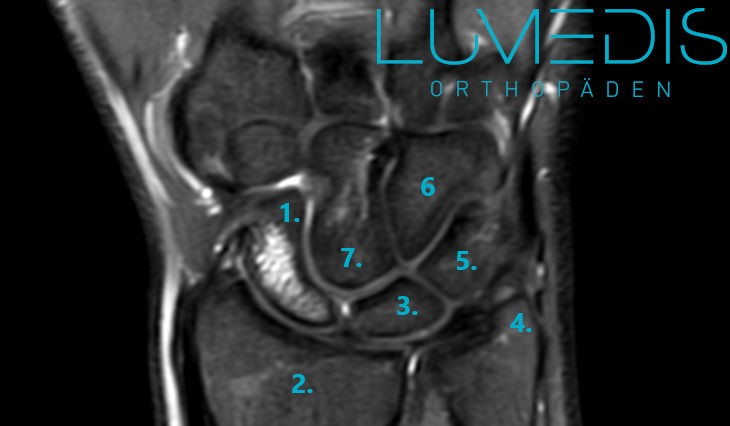

MRT eines Handgelenk mit Handwurzel mit Bandverletzung